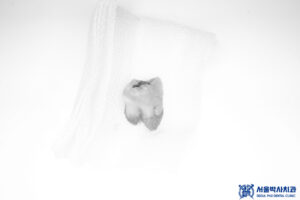

앞 치아는 신경치료가

되어있는 치아라

치아를 분할하며

발치를 진행하였습니다.

그리고 치근낭 적출도 함께 진행하여

염증을 깨끗하게 소파하였습니다.